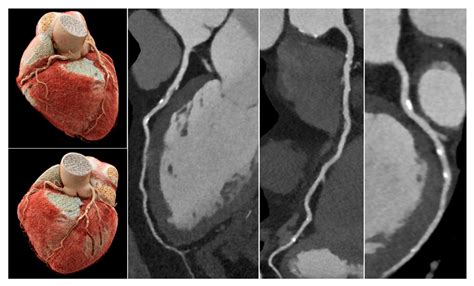

When it comes to diagnosing heart conditions, precision is paramount. A Cardiac CT, also known as a coronary computed tomography angiography (CCTA), has revolutionized the way medical professionals visualize the complex structures of the heart. By utilizing advanced X-ray technology coupled with powerful computers, this non-invasive diagnostic tool creates detailed, three-dimensional images of your heart, its arteries, and the surrounding tissues. Whether you are experiencing unexplained chest pain or have known risk factors for cardiovascular disease, understanding how this procedure works can help alleviate anxiety and prepare you for your medical journey.

At its core, a Cardiac CT scan is an imaging test that allows cardiologists and radiologists to see if your coronary arteries are narrowed or blocked by plaque buildup—a condition known as atherosclerosis. Unlike traditional stress tests, which provide functional information about how your heart handles exertion, a cardiac CT provides anatomical information. It captures images of the heart while it is beating, using sophisticated gating technology to synchronize the image acquisition with your heart rhythm.

This technology is particularly effective at identifying early-stage heart disease before symptoms manifest. By visualizing the calcified and non-calcified plaque within the arterial walls, physicians can initiate preventative treatments far earlier than previously possible.

Once the scan is complete, the images are sent to a radiologist or a specialized cardiologist who analyzes the anatomy of your coronary arteries. They will look for the presence and extent of plaque, the degree of arterial narrowing (stenosis), and the presence of any calcium deposits. You will receive a formal report, and your primary doctor will discuss the findings with you to determine the next steps in your care plan. Depending on the findings, these steps may include lifestyle modifications, cholesterol-lowering medication, or further diagnostic testing.